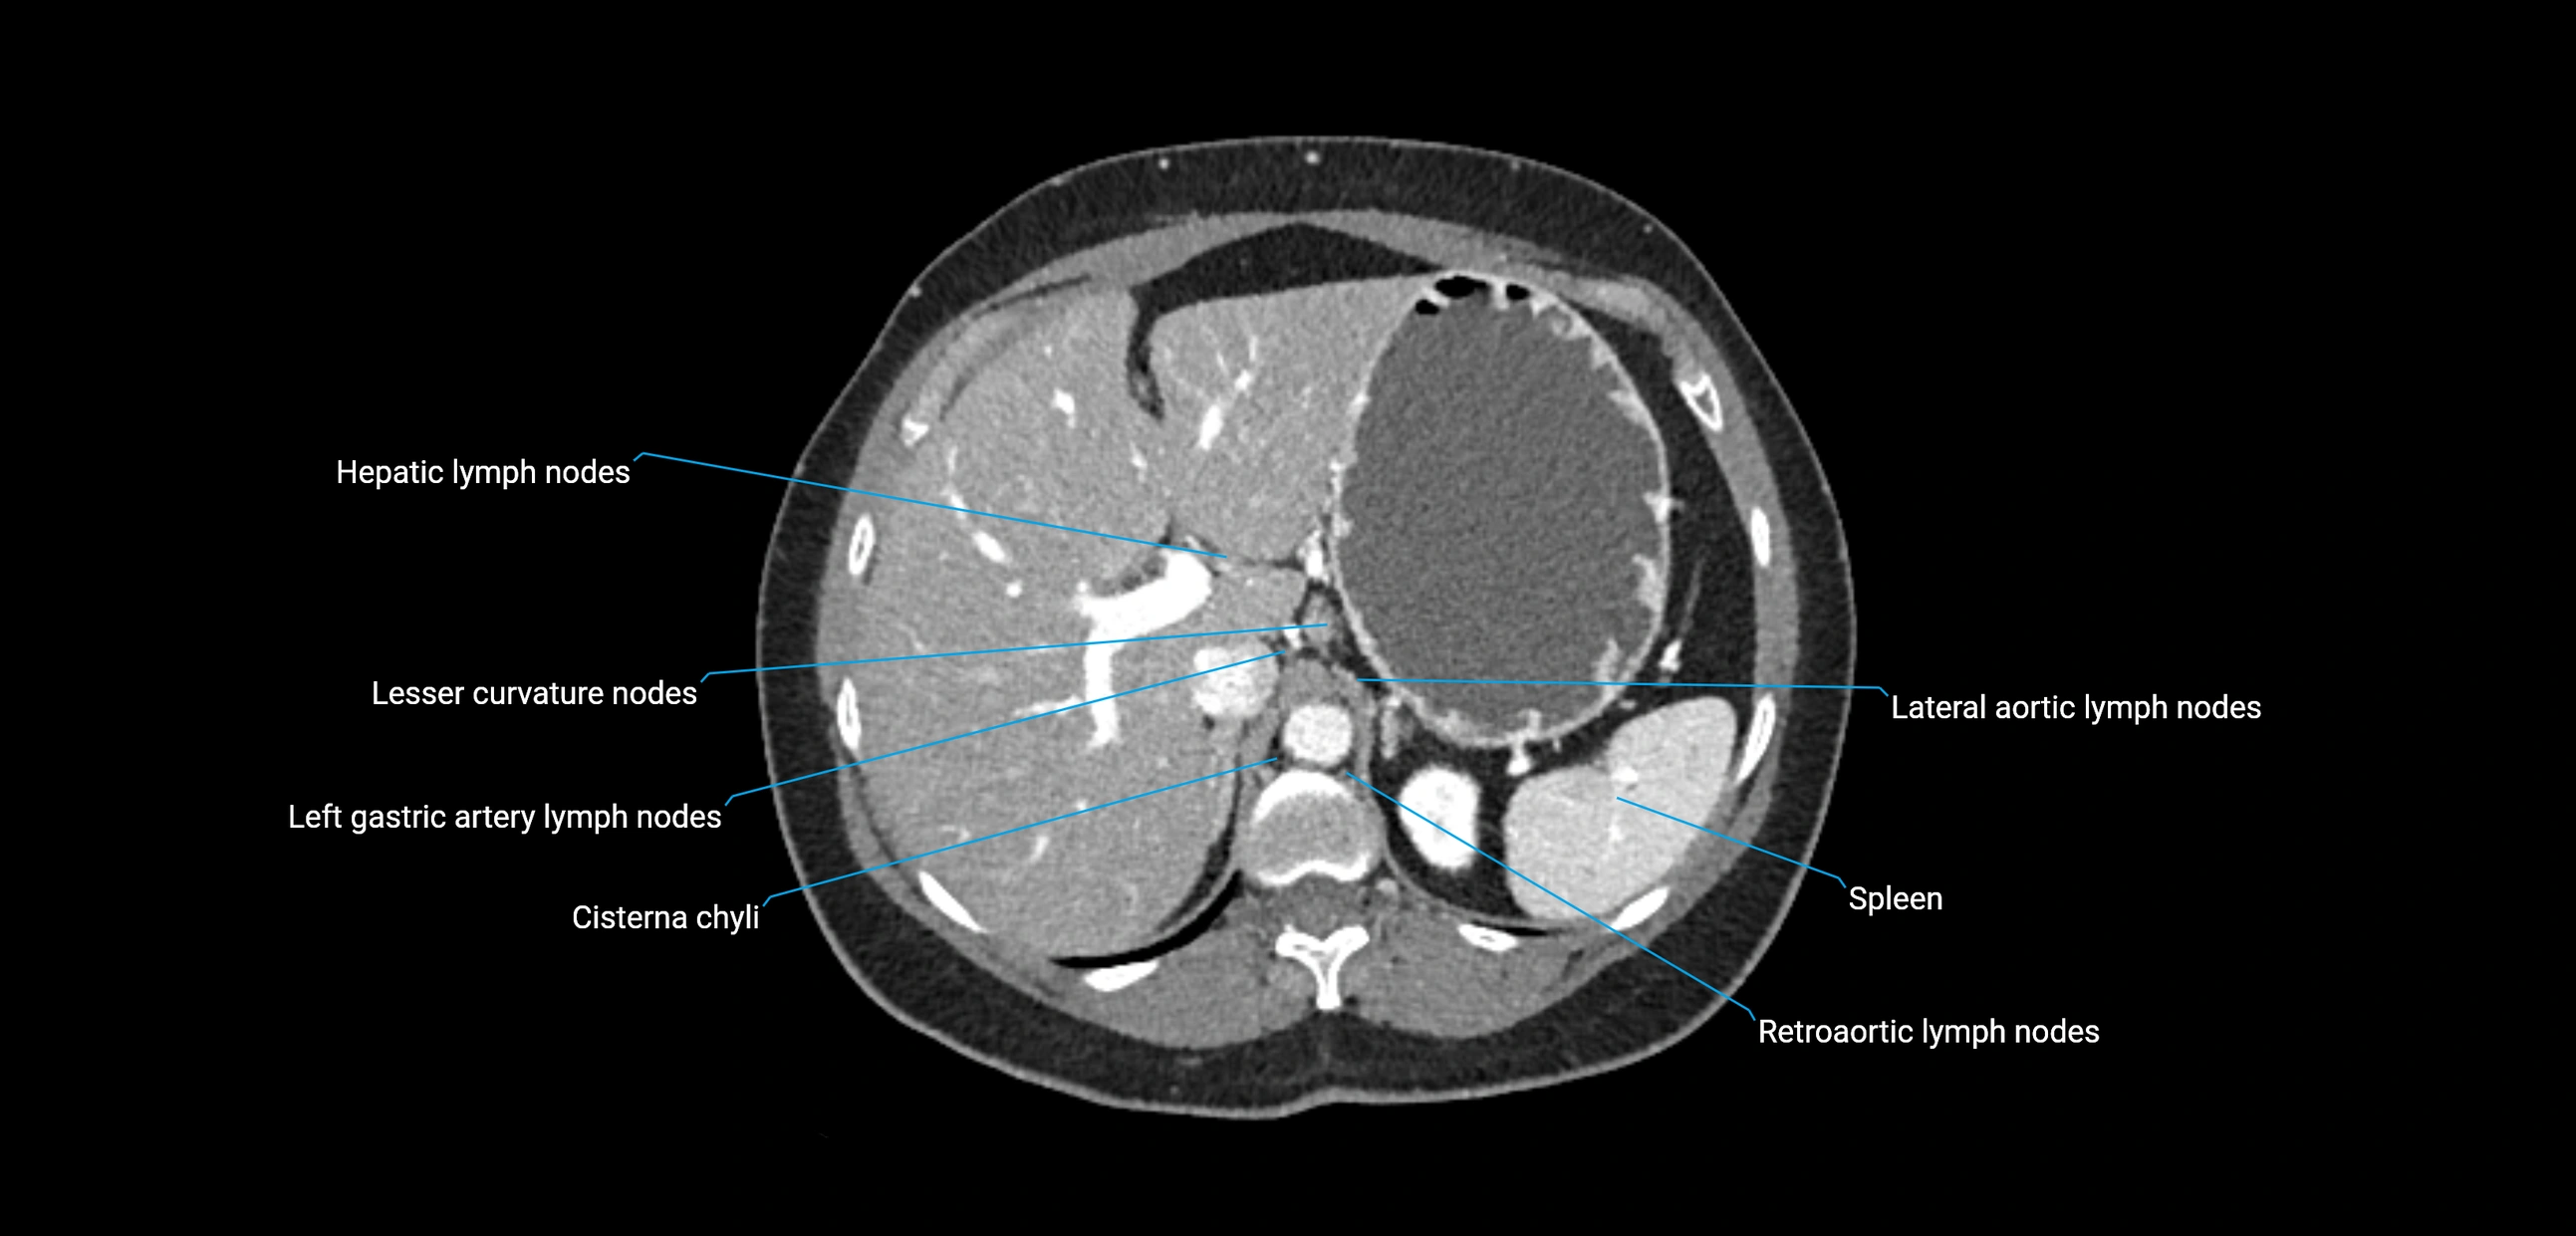

MRI images

image